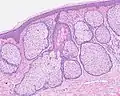

H&E staining of biopsied lesion of sebaceous hyperplasia: Note the multiple, mature sebaceous lobules attached to the central dilated duct in the upper dermis.